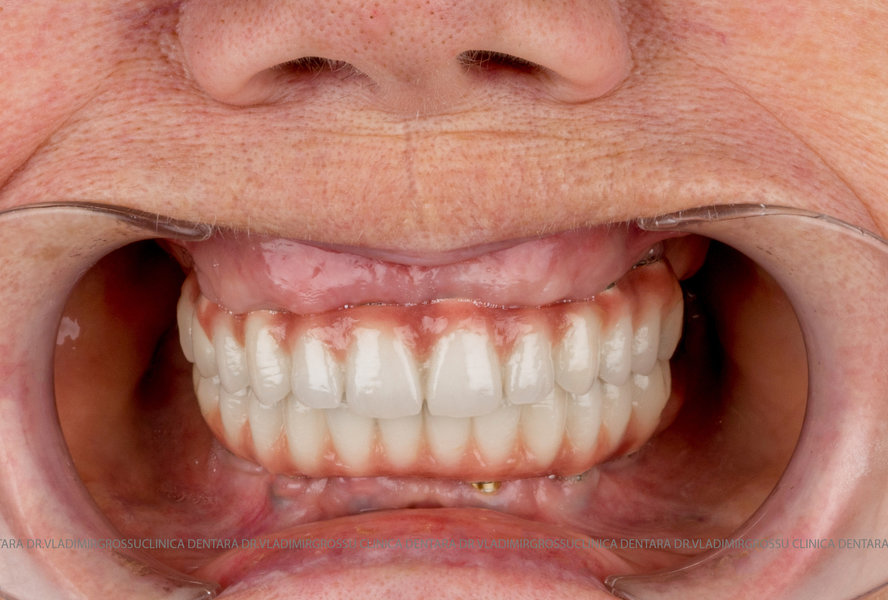

Cazuri clinice conceptul All-on-6